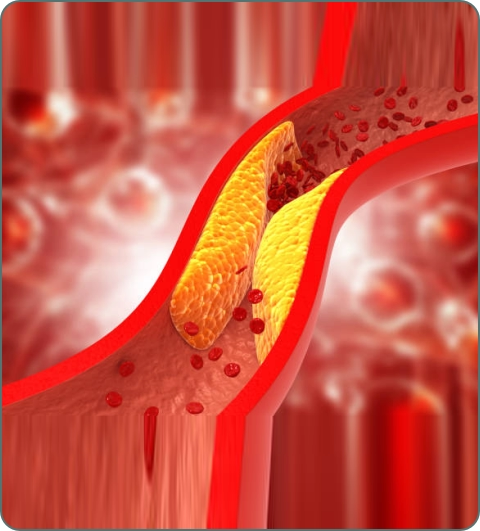

Coronary Artery Disease (CAD)

Blockage or narrowing of coronary arteries due to plaque buildup. Common in India due to lifestyle factors. Symptoms: chest pain (angina), shortness of breath, fatigue, heart attack risk.